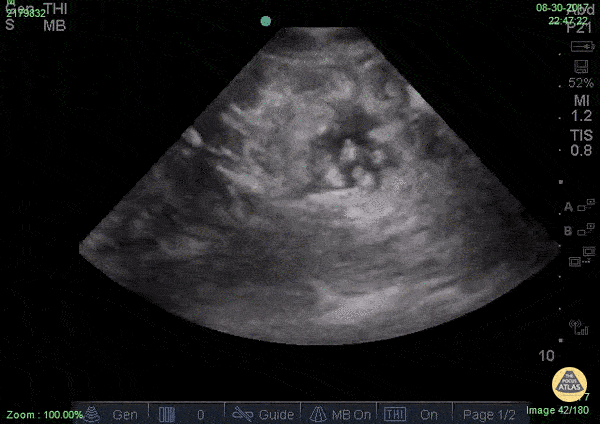

WCUME17 submission: "Creative Caption" "Well hellllllo there...I'm so ASCITED to see you!" Patient with ascites and a surprising greeting on POCUS. Dr. Stephen Alerhand - Mount Sinai Hospital